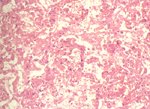

剖檢時鼻腔可見大量血樣鼻液蓄積,雙肺均呈明顯廣泛散播性潮紅及出血灶,此病變主要位於膈葉,小葉間膈明顯。 三、 組織病變: 鏡下可見局部肺實質出現出血壞死灶。肺小葉間隔水腫液蓄積。 四、 微生物學檢查:

自肺部分離出很純之Actinobacillus pleuropneumonia(舊屬名Haemophilus) 五、 診斷: 豬嗜血桿菌胸膜肺炎 註:以圖片說明不同時期之病變:1.2.3.為甚急性型;4.5.為急性型;6.7.為亞急性型;8.為慢性型。